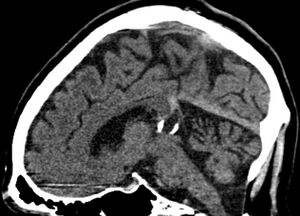

Verkalkte Corpus pineale Zyste sagittal.jpg

Calcified cyst of pineal gland in CT. Sagittal MPR.